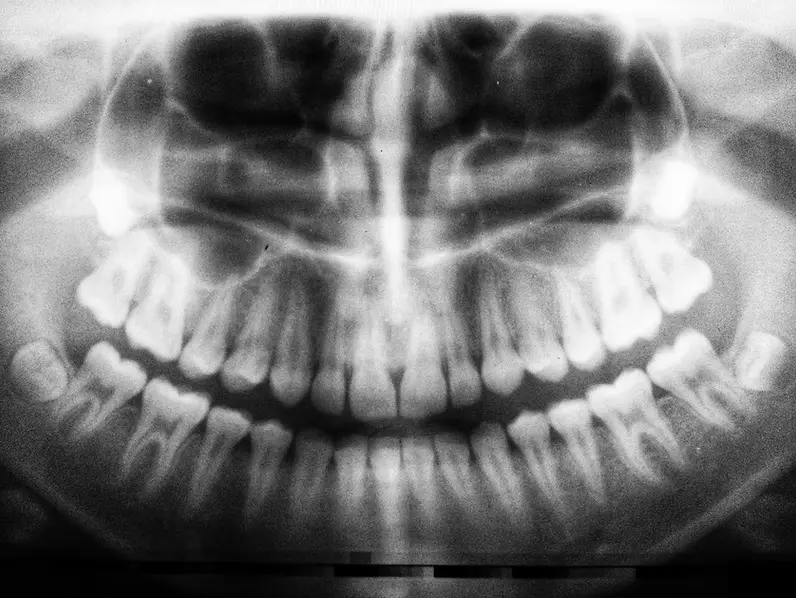

Orthoganathic means correcting deformities of the jaw and the associated malocclusion

Orthodontic problems involving severe jaw growth discrepancies can be corrected only after growth has been completed.

Sometimes the size of the upper and lower jaws do not match closely enough to allow for a satisfactory bite or meshing of the front or back teeth. This can result in both functional as well as esthetic problems. In these cases, the only way to achieve an ideal bite is to straighten the teeth and then perform surgery on the jaws to correct the growth concern. The specific surgical procedure depends upon the unique nature of the growth problem. A detailed clinical examination and analysis of diagnostic records will be made by the orthodontist and surgeon. The diagnosis and comprehensive treatment recommendations will be presented to the patient in a joint meeting. In most cases the patient will be able to view a computer-based surgical prediction of how the face might look following completion of treatments proposed by both surgical and orthodontic teams.